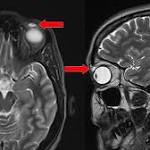

- Woman's painful cyst turns out to be contact lens embedded in eyelid for 28 years fox13now.com

- Woman Gets Contact Lens Stuck In Eye For 28 Years HuffPost

- Contact lens found lodged in woman's eyelid 28 years after she 'lost' it, doctors report USA TODAY

- Doctors remove contact lens unknowingly stuck in woman's eyelid for 28 years Atlanta Journal ConstitutionFull coverage